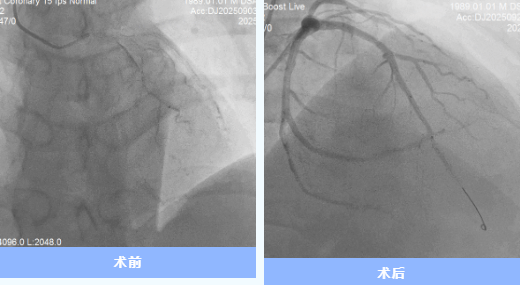

9月29日世界心臟日,35歲的代先生從隨州市中心醫(yī)院康復(fù)出院,將錦旗交予醫(yī)護(hù)人員手中。這背后,是一場由多學(xué)科協(xié)作的20余天的“生命保衛(wèi)戰(zhàn)”。 01雷霆救治:與死神競速 9月3日17時(shí),代先生因“胸痛不適1天,加重1 ...